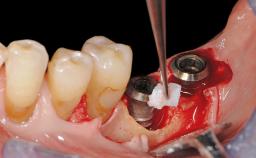

In this case, Myroslav Solonko, Ignacio Sanz Sánchez and Mariano Sanz present a treatment that aims to eliminate exposed implant threads by modifying the implant surface, converting a moderately-rough surface into a smooth surface.

A 63-year-old male patient was referred to the post-graduate periodontal clinic of the Complutense University of Madrid for the treatment of peri-implantitis. According to the patient’s record, all his maxillary teeth had been extracted ten years previously due to severe periodontitis, and a full-mouth implant-supported restoration on eight implants was placed. No supportive periodontal therapy was provided apart from occasional check-ups by the restorative dentist.